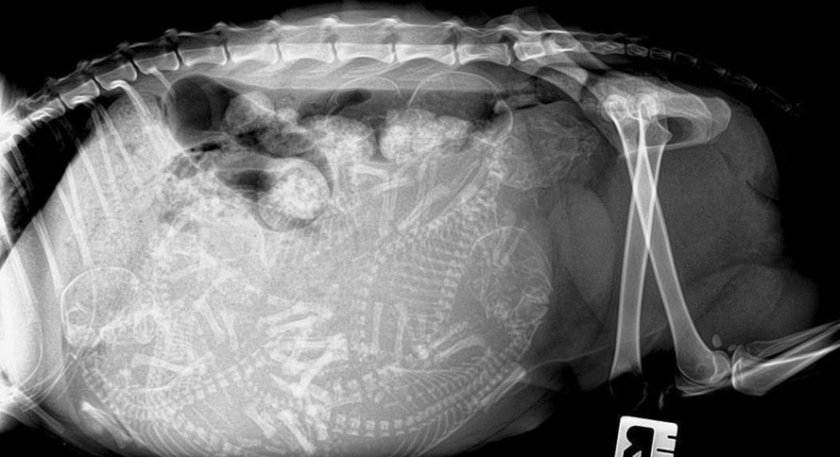

Ваша домашняя любимица начнет прибавлять в весе на 4-5-ю неделю, вес увеличится на один-два килограмма в зависимости от количества котят. На рентгеновском снимке можно увидеть скелетную структуру котят на 44-й день, но не делайте рентген без крайней необходимости.

С середины беременности можно отметить изменения в кошачьем организме и на рентгене. Чтобы излучение не нанесло вред котятам, метод лучше использовать не ранее 40 дня с момента вязки. В это время на снимке уже видны скелеты малышей.